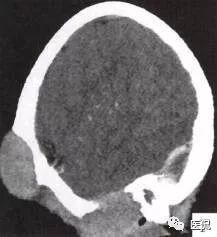

颅脑CT示:图A〜D,CT平扫示左侧额骨、蝶骨见溶骨性骨质缺损,边界清晰,周围无硬化边,伴有软组织肿块向脑外生长,边缘光滑,脑内无明显侵犯;

图E、F,横、 矢状位CT增强示软组织肿块轻度均匀强化,两病灶间亦见强化软组织影;

2.定位诊断:额骨、蝶骨均可见局限性骨质破坏,穿破颅骨内外板,见软组织肿块突向脑外;肿块与硬脑膜界限清楚,脑实质无侵犯;应考虑颅骨来源,向颅外侵犯。